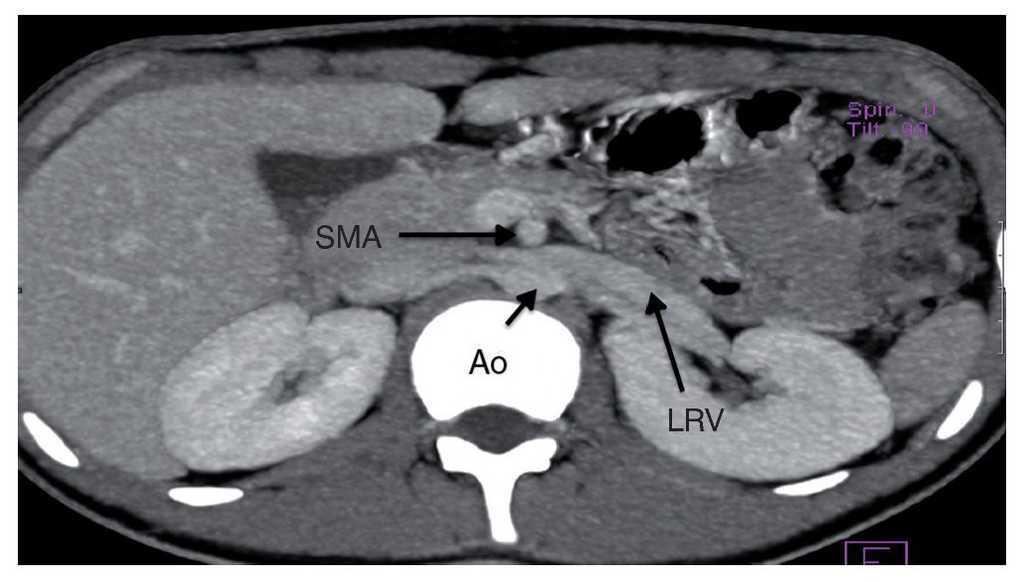

The duodenum and the left renal vein (lrv) occupy the vascular angle made by the superior mesenteric artery (sma) and the aorta. Superior mesenteric artery (sma) syndrome, also known as wilkie’s syndrome or benign duodenal stasis, is a rare benign. The optimal treatment includes open decompression of the left renal vein with renal vein transposition or gonadal vein transposition,. Superior mesenteric artery syndrome is the compression of the third portion of the duodenum between the superior mesenteric. Nutcracker phenomenon refers to compression of the left renal vein, most commonly between the aorta and the superior mesenteric artery, with. The duodenum and the left renal vein occupy the vascular angle made by the superior mesenteric artery and the aorta.

Computed tomography angiography showing the compression of the duodenum Nutcracker Syndrome Duodenum Superior mesenteric artery (sma) syndrome, also known as wilkie’s syndrome or benign duodenal stasis, is a rare benign. The duodenum and the left renal vein occupy the vascular angle made by the superior mesenteric artery and the aorta. The duodenum and the left renal vein (lrv) occupy the vascular angle made by the superior mesenteric artery (sma) and the aorta.. Nutcracker Syndrome Duodenum.